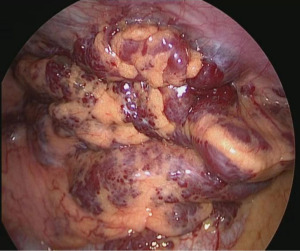

A 40-year-old patient underwent chest computed tomography (CT) during a routine medical examination, and an anterior mediastinal mass was detected. The patient had undergone fracture fixation one year earlier for a right calcaneal fracture, and the internal fixation in the calcaneus was not removed. Otherwise, the patient had no other past medical history, his physical examination and laboratory data were normal, he had no history of chronic or genetic disease, and a chest radiograph showed no abnormalities. A CT scan revealed that a mediastinal mass was located in the anterior mediastinum. The mass range was approximately 9.2 cm × 3.9 cm × 3.6 cm. The CT scan also showed that the mass had a smooth surface and heterogeneous contents. The upper border of the tumour was from the sternal angle and the inferior border of the tumour was at the aortic outflow. The contrast-enhanced CT scan revealed uneven delayed enhancement shadows with multiple punctate calcifications (Figure 1). The patient was unable to undergo magnetic resonance imaging (MRI) due to the internal fixation in the right calcaneus. According to preoperative examinations and imaging reports, we suspected that the mass in the anterior mediastinum was a haemangioma. Mediastinal haemangiomas require differentiation from mediastinal cysts, neurogenic tumours, teratomas, and lymphomas. For diagnosis and treatment, we performed a minimally invasive thoracoscopic mediastinal tumour resection and sent the resected tumour for postoperative pathological examination. After the patient received general anaesthesia and a double lumen endotracheal tube was placed, we introduced a thoracoscope using a trocar in the seventh intercostal space at the posterior axillary line. We placed two other working trocars in the third and sixth intercostal spaces at the anterior axillary line in order to insert the dissecting instruments. The mass was located in the anterior mediastinum encased in a vascular cluster (Figure 2). We opened the mediastinal pleura with an electrocoagulation hook, and the anterior mediastinal haemangioma was resected along the mediastinal adipose tissue. We found that the tumour adhered closely to the superficial pericardium vessels and likely served as a source of vascular supply for the tumour; therefore, these vessels were carefully removed by dissection and the total thoracoscopic resection of the suspected mediastinal haemangioma was complete.

The resected specimen measured 15.0 cm × 6.0 cm × 1.4 cm and was surrounded by pericardial adipose tissue and haemorrhagic and transparent thrombosis (Figure 3). A large number of thick, sponge-like vascular sinuses were found during the mirror-image inspection of the tumour. Based on these findings, the tumours were diagnosed as mediastinal sponge haemangiomas. The patient recovered without postoperative complications and was discharged post-operative day four. The patient was examined one month later, with follow-up visits scheduled every 6 months thereafter. At present, 24 months after surgery, no recurrence has been observed and the individual continues to be carefully monitored as an outpatient. The patient has recovered well and is able to perform heavy physical work without reporting any adverse effects or complications. All procedures performed in this study were in accordance with the ethical standards of the institutional and/or national research committee(s) and with the Helsinki Declaration (as revised in 2013). Written informed consent was obtained from the patient for publication of this case report and accompanying images. A copy of the written consent is available for review by the editorial office of this journal.